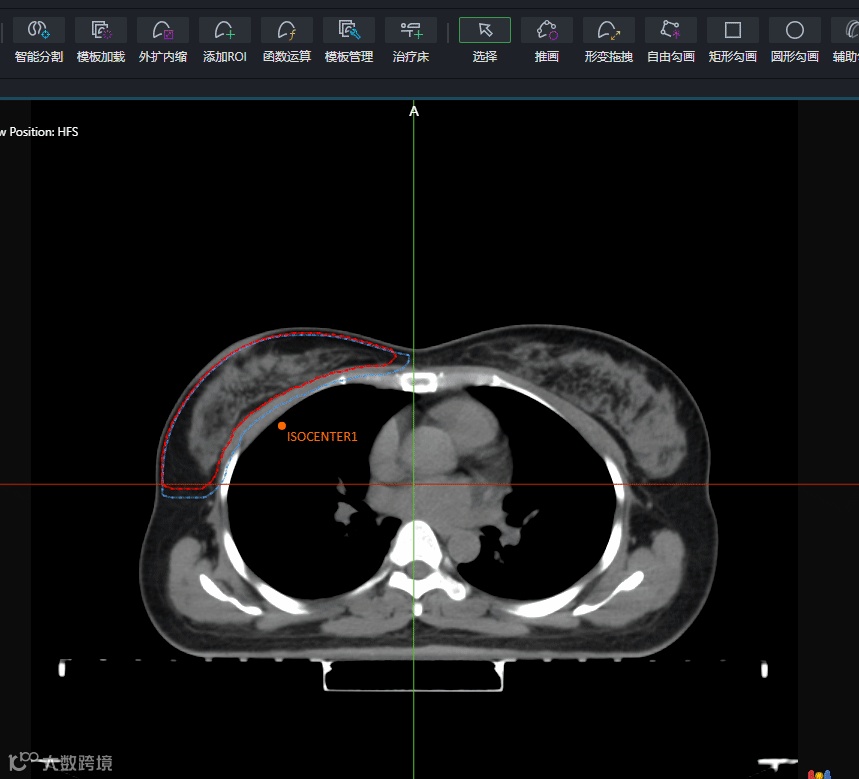

函数支持显示为“是”的ROI,表示该ROI与其它ROI之间有函数关联。如,CTV外扩5mm生成了PTV,保存为模板之后,PTV的生成方式就会显示为“函数支持”。在调用模板时,会先生成轮廓为空的CTV和PTV。在勾画完CTV后,选中PTV时,会看到列表右上角的<ROI表达式更新>按钮会点亮起,点一下它,外扩后的PTV轮廓就“刷”出来了。

这个方法不只可以用于靶区之间的外扩关系,还可用来生成更多更复杂的辅助结构,如扩环、作辅助优化的靶区、生成Fix结构等,比如下图所示。